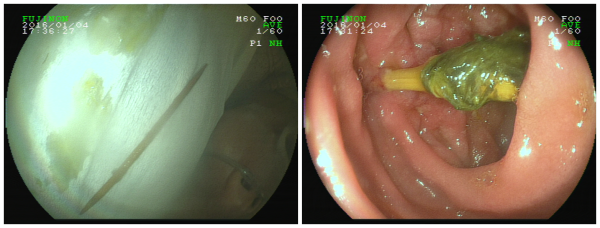

由于异物所在位置为十二指肠球降交界处,异物尖部已经插入小肠壁,若操作稍有不慎,异物尖部可能会划破肠壁及周围的脏器,引起肠穿孔或脏器大出血。在胃镜视野下,袁主任发现嵌在林先生患处的是一根包裹着食物残渣和胆汁的牙签!经过一个多小时细心谨慎的手术,一根约6.5cm的牙签被医生从林先生体内的十二指肠中取出,手术很顺利。术后,林先生便不再感觉腹痛,医生表示,再住院观察两天,林先生便可以出院了。

内镜视野下林先生体内的牙签